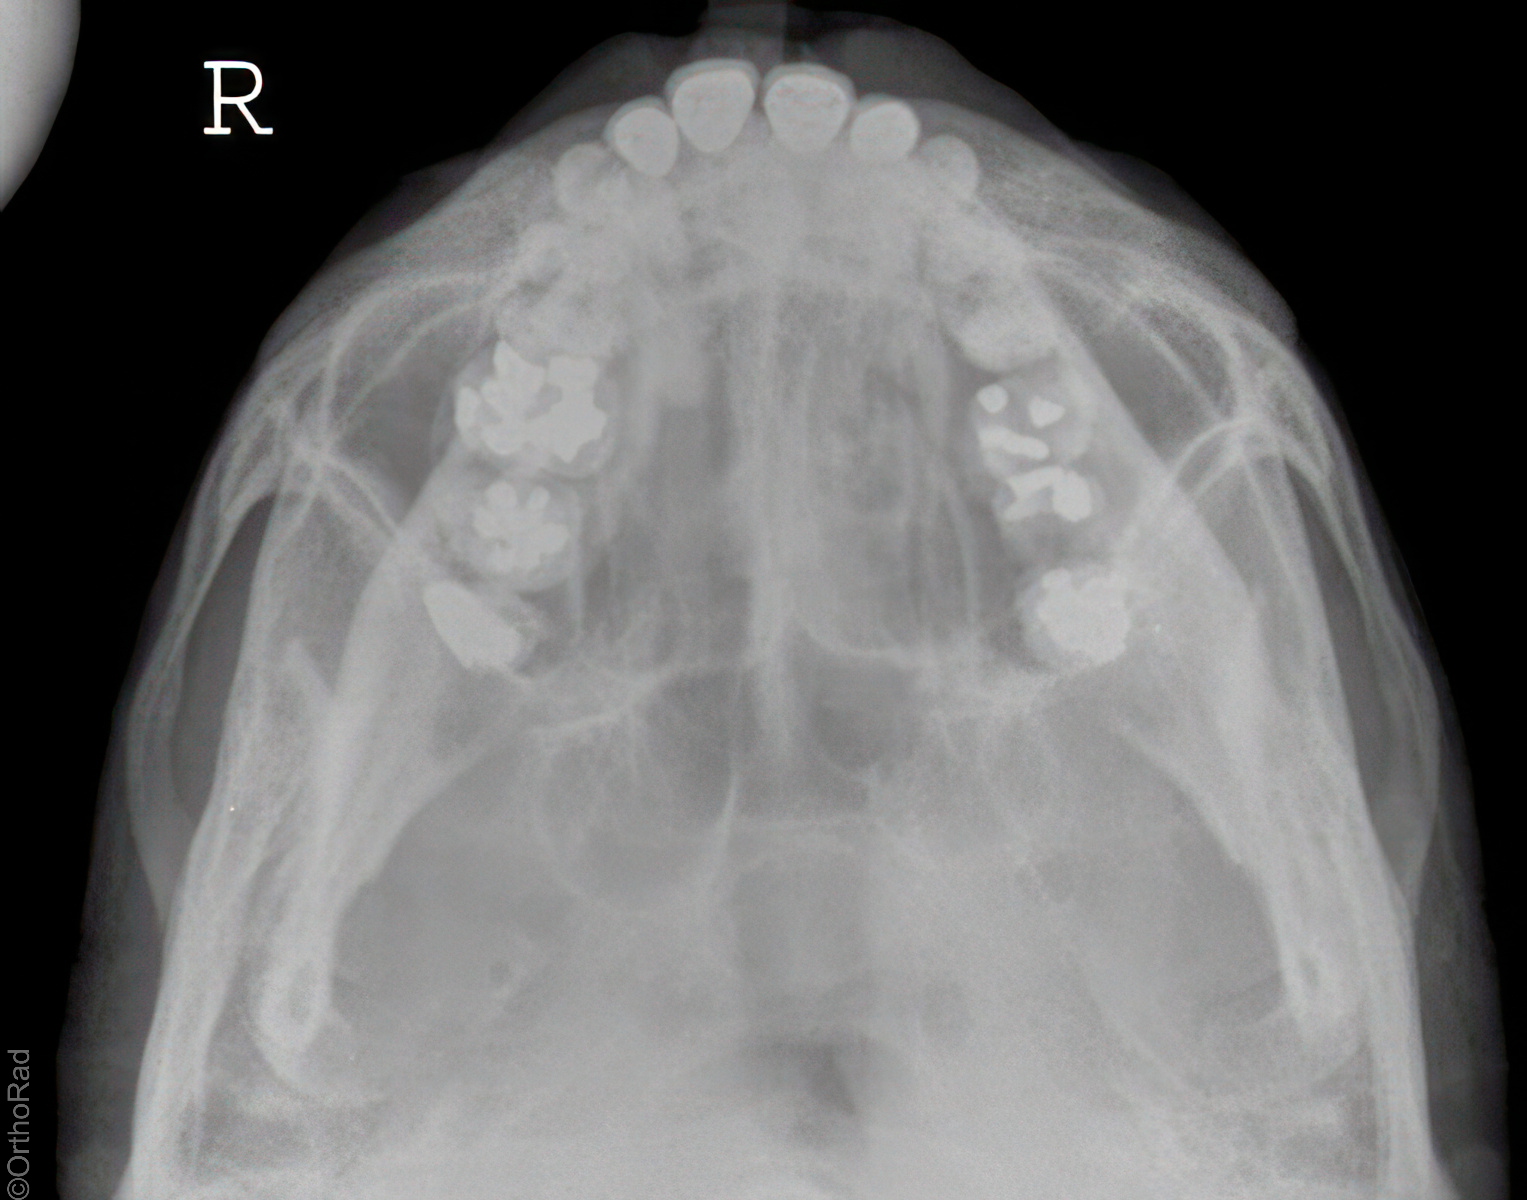

Jochbogen axial (Henkeltopfaufnahme)

Technik

• FDA: 80-90 cm

• Ausgangsformat: 18/24 quer

• Röhrenkippung: 45° caudo-cranial

• Übertischaufnahme

Indikation

Fraktur

Lagerung

Rückenlage

Schulter stark unterpolstert

kleiner Keil unter dem Kopf

45° Keil unter den Bildempfänger

Bildempfänger liegt unmittelbar am Haaransatz an

Kinn angehoben, bis Deutsche Horizontale (unterer Orbitaboden-Gehörgang-Linie) parallel zum Bildempfänger verläuft

Mund geöffnet

Zentralstrahl

Querstrahl: mittig zwischen Gehörgang und äußerer Augenwinkel

Längsstrahl: Medianebene

Einblendung

cranial = Augenbraue, caudal = Tragus

Bemerkung

Finger-Schatten-Test; Mund muss geöffnet sein.

Qualitätskriterien

Freie und übersichtliche Projektion des Jochbogens.